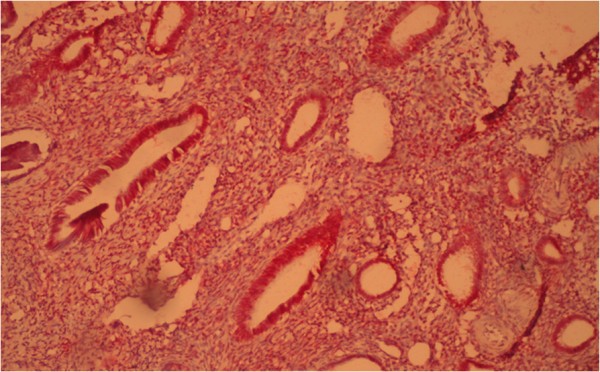

Histologically, we determined in atypical endometrial hyperplasia the glands with numerous ramifications and papillary projections that protruded into the lumen of glands; they are strongly sinuous, with irregular shape. Here and there, glands are closely located to each other without stromal layers and are separated by a narrow strip of connective tissue only. The epithelial cells of glands acquired the features of tumor processes: reduction of nuclear/cytoplasmic ratio, hyperchromatosis, nuclear polymorphism, etc. There were proliferation and increased mitotic activity and abnormal mitosis. Atypical endometrial hyperplasia is shown in Figure 12.

Figure 12

Atypical glandular hyperplasia of the endometrium. Coloring by hematoxylin-eosin (×40).